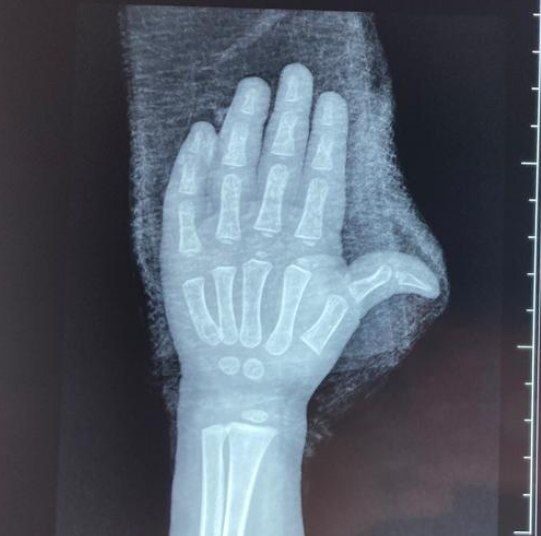

Alabí detalló que gracias a la oportuna intervención de cirujanos plásticos, se logró salvar los dedos de la menor «reduciendo cualquier riesgo de secuela que pueda afectarle en un futuro».

Afortunadamente, y tal como lo dijo Alabí, la niña no tendrá secuelas físicas en el futuro, por este accidente.